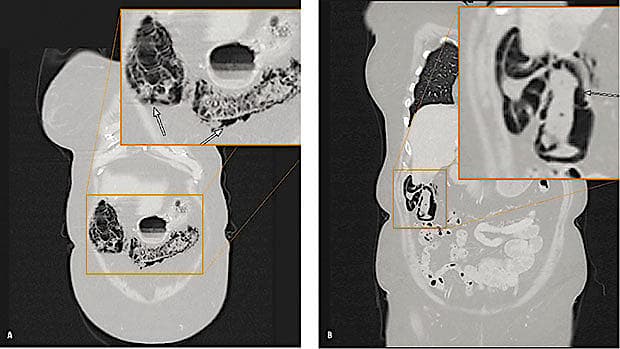

En 76-årig kvinde, der nogle måneder tidligere havde fået kemoterapi pga. dissemineret lungecancer, fik foretaget kontrol-CT af thorax og abdomen. CT’en viste intramural luft i colon ascendens og transversum (A). Fundet rejste mistanke om tarmiskæmi. Klinisk og paraklinisk havde patienten dog ingen tegn på dette. Ved en gennemgang af en seks måneder ældre CT (B) fandtes ligeledes luft i tarmvæggen på samme niveau, dog i mindre grad. Tilstanden blev tolket som pneumatosis intestinalis (PI) som bivirkning af kemoterapi, og kirurgisk intervention var således ikke nødvendig.

PI er defineret som tilstedeværelse af luft i tarmvæggen. Som benigne årsager til PI kan nævnes: idiopatisk form, organtransplantation eller kemoterapi. Som livstruende årsager kan nævnes: intestinal iskæmi, strangulationsileus og infarkt. PI er således ikke er en sygdom, men et tegn, der skal sammenholdes med patientens kliniske og parakliniske tilstand. CT er den undersøgelsesmetode, som er mest sensitiv til påvisning af PI, og den øgede brug af CT og anvendelsen af nye medikamenter og kirurgiske procedurer har medvirket til, at der er fundet en stigende incidens af PI [1, 2].